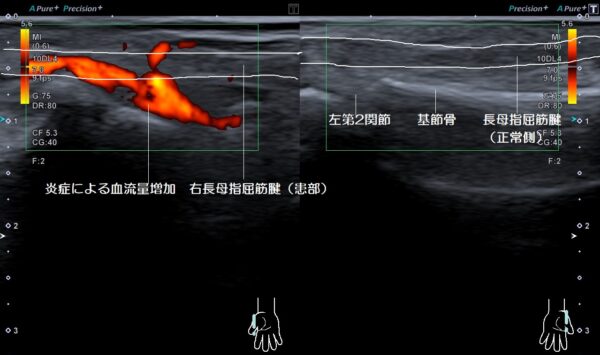

超音波画像検査を行うと右長母指屈筋腱の周囲が過剰な炎症(傷んだ組織を治す生体反応)を起こし、血流量が通常よりも増加していました。

【施術】手の平側の親指の第2関節が腫れて皮膚の熱が高くなっています。親指の第2関節を曲げようとするとカクッとなる時の痛みが怖くて曲げられませんでした。

指を曲げ伸ばしする時にカクッという衝撃と共に痛みを伴う腱鞘炎をばね指(弾発指)と言います。